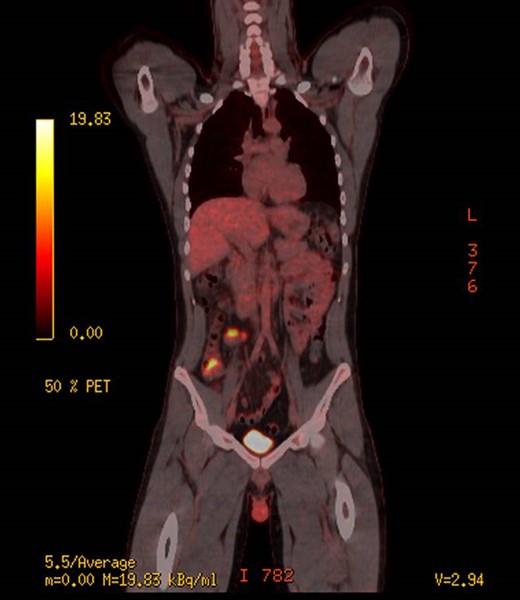

The patient underwent further work up with tumour markers, of which his AFP was positive at 2145 IU/ml. His other tumour markers including, carcinoembryonic antigen (CEA) and human chorionic gonadotropin (HCG) were negative. Given the unusual histopathology the patient was thoroughly reexamined looking for evidence of other lesions. Clinically the patient had no evidence of testicular masses, which was confirmed with a testicular ultra sound demonstrating no evidence of masses or lesions. A brain magnetic resonance image (MRI) was performed showing no evidence of pineal lesions. A positron emission tomography (PET) scan was performed showing increased fluorodeoxyglucose (FDG) uptake in the caecum, and nearby in the mesentery (medially) and possibly two small lymph nodes anterior to the caecum (Fig. 2). After discussion at a multi-disciplinary meeting with medical/radiation oncologists and surgeons, it was concluded that the primary was likely in the caecum. He was subsequently consented for a laparoscopic right hemi-colectomy.

PET scan, demonstrating increased uptake in the caecum and likely mesentery lymph nodes.